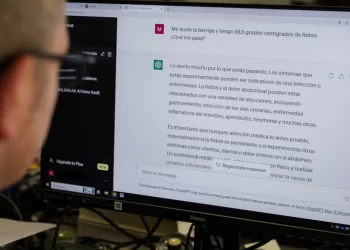

Read moreDetailsCrece la cantidad de mexicanos que usan la IA para consultas médicas

La encuesta de Funsalud revela que la IA pasó del octavo al tercer lugar entre las herramientas digitales más utilizadas,...